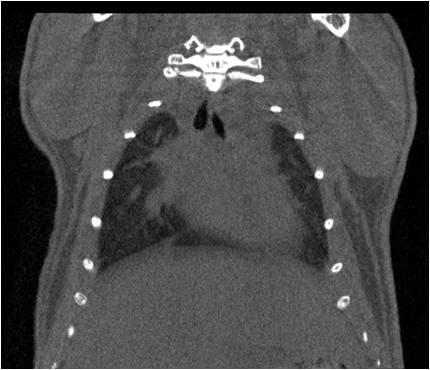

胸部和心血管的層析成像 胸部和心血管的3D圖像

心血管.jpg 心血管1.jpg